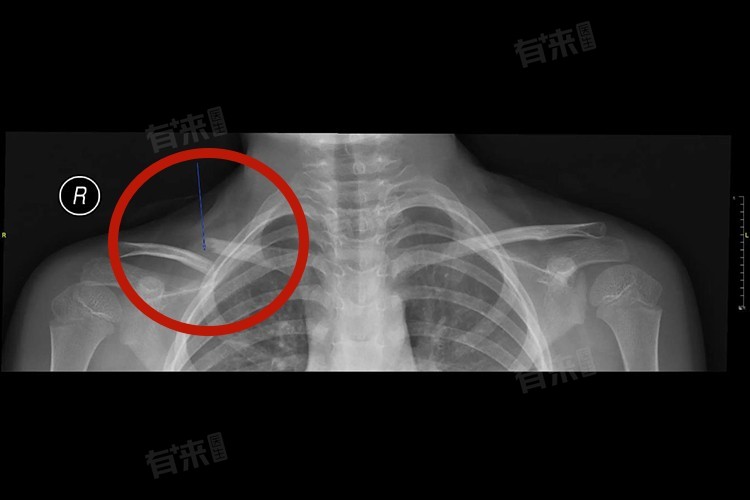

3、切开复位内固定术:对于移位明显、成角畸形或粉碎性骨折等严重情况,切开复位内固定术是常用的治疗方式。手术通过切开皮肤、肌肉等软组织,暴露骨折部位,进行复位和内固定。内固定材料可以是钢板、螺钉或克氏针等,具体选择取决于骨折的类型和位置。手术后患者需要佩戴外固定装置,如石膏背心一段时间,促进骨折愈合。